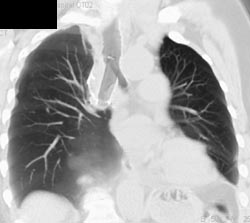

Collapse of Right Upper Lung Bronchus